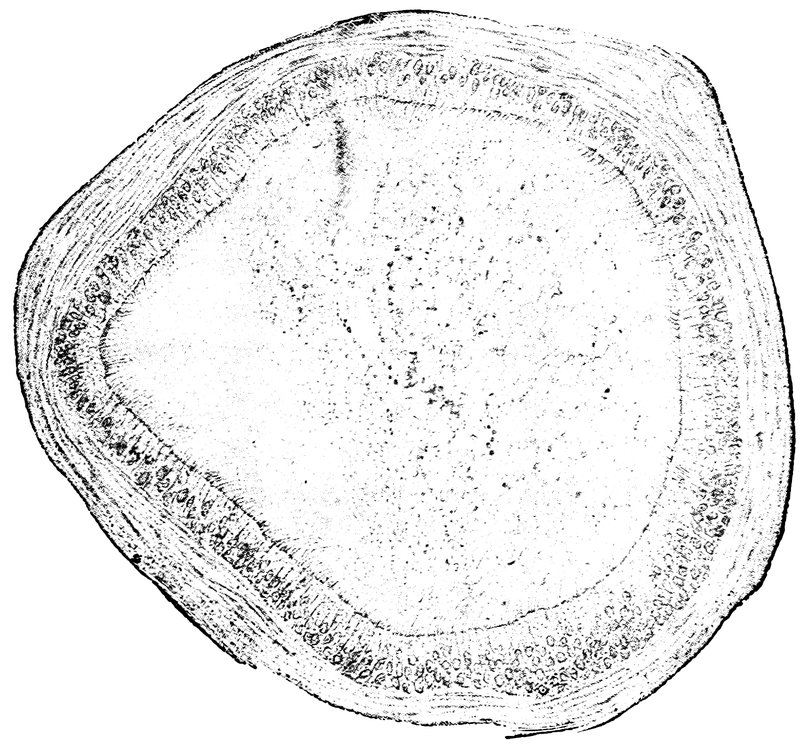

84. Sagittal section through the ovary of a girl aged sixteen 583

85. Sagittal section through the ovary of a woman aged seventy-two years 584